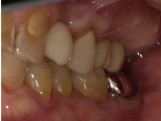

| 治療ケース | 下顎:右下6 静脈内鎮静・局所麻酔を行い、1本のインプラントを埋入(1回法)。3か月後にプロビショナル装着。5ケ月後に上部構造オールセラミック装着。 |

| 症状 | 右下6欠損。 |

| 治療結果 | 歯が無い所に歯を入れたいという主訴でご来院。骨質も良く良好な初期固定が得られ1次手術、2次手術を同時に行う1回法で手術を行えました、治療期間も短縮できしっかり咬めるようになった大変満足されています。 |

| 治療開始月 | 2018年11月 |

| 治療期間 | 約5ヶ月 |